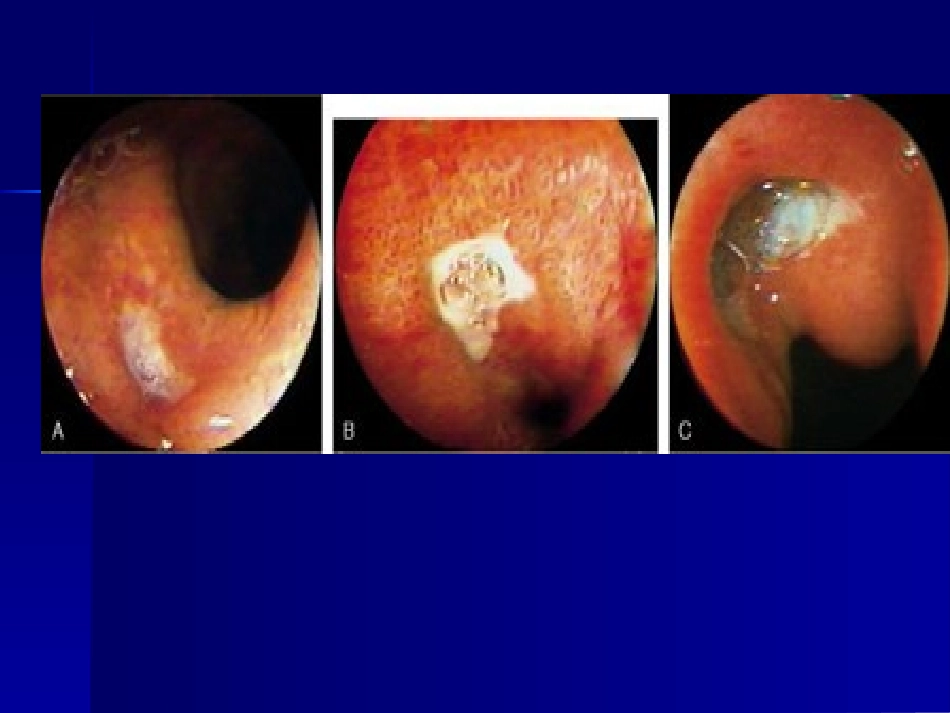

流行病学流行病学发病呈下降趋势发病呈下降趋势世界性分布.临床上GU多于DU,两世界性分布.临床上GU多于DU,两者之比者之比2-2-3:1.DU好发于青壮3:1.DU好发于青壮年,GU发病年龄较迟,平均晚十年。年,GU发病年龄较迟,平均晚十年。消化性溃疡的发作有季节性,秋冬和冬消化性溃疡的发作有季节性,秋冬和冬春之交比夏季常见。春之交比夏季常见。病因和发病机制病因和发病机制平衡学说平衡学说攻击因子攻击因子——胃酸、胃蛋白酶、微生物、胃酸、胃蛋白酶、微生物、胆盐、乙醇、药物、其他有害物胆盐、乙醇、药物、其他有害物防御修复因子防御修复因子——粘液/碳酸氢盐屏障、粘液/碳酸氢盐屏障、粘液屏障、粘液血流量、细胞更新、前列腺粘液屏障、粘液血流量、细胞更新、前...